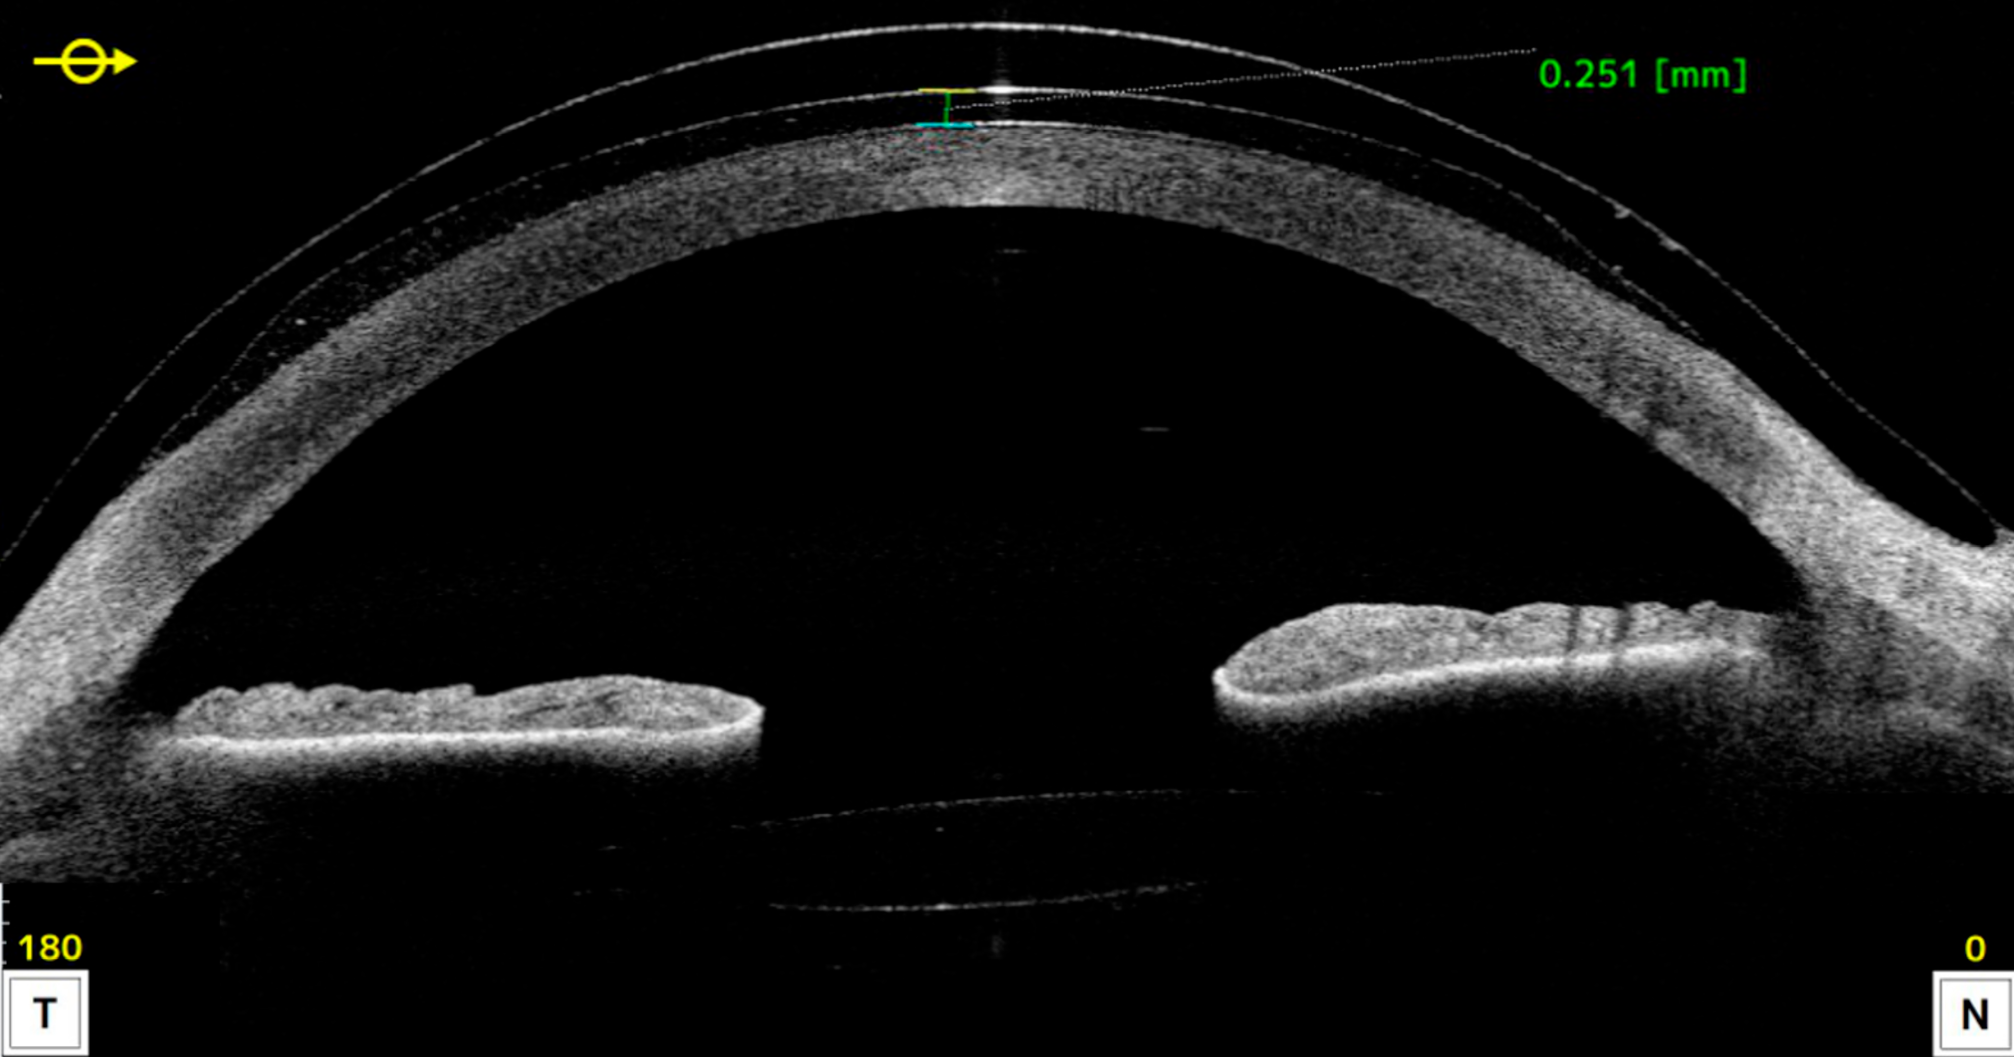

Figure 2. Schisis maculaire myopique en imagerie OCT ultra grand champ objectivant l’adhérence pathologique du vitré, avec des tractions exercées sur les vaisseaux rétiniens (tête de flèche), et l’étirement de la rétine externe maculaire associé à un détachement fovéolaire (flèche).